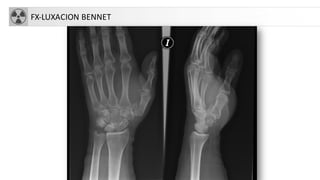

FX-LUXACION BENNET

Fragmento del meta en

zona cubital unido a

trapecio, el resto se

desplaza.